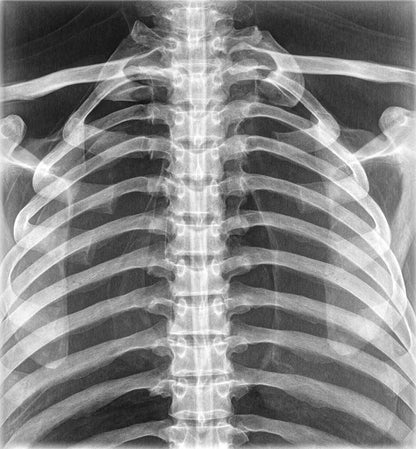

The whole-body X-ray phantom serves for practical training in projection radiography as well as in positioning and positioning techniques. It enables the production of realistic X-ray images under training conditions and depicts anatomical structures in their natural size.

The phantom contains a natural human skeleton. Additionally, the outlines of the larynx, lungs, heart, and kidneys are integrated, appearing as shadows on the X-ray images. This allows for the creation of images that accurately reflect the conditions found in patients. The use of a real skeleton enables the identification of bony landmarks that are not visible in plastic models.